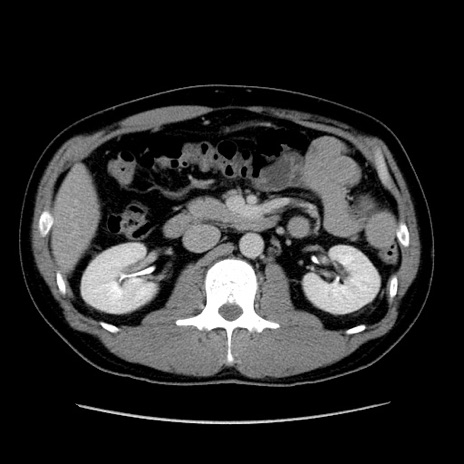

症例4(横断像)

【症例】30歳代男性

【主訴】腹痛、嘔吐

【現病歴】昨晩から突然の腹痛あり、その後嘔吐、軟便も出現。腹痛が改善しないため救急搬送となる。2日前にしめ鯖の食事歴あり。

【身体所見】意識清明、苦悶様、BP 135/90mmHg、BT 35.7℃、腹部:平坦、やや硬、心窩部〜臍部に自発痛、圧痛あり、筋性防御+、反跳痛-

【データ】WBC 8100、CRP 0.57